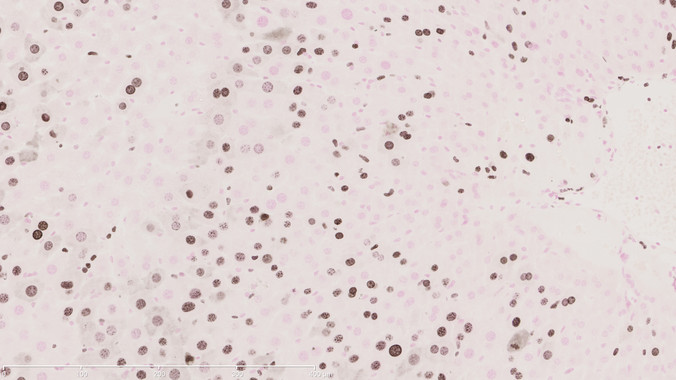

Immunotherapy: Boosting the immune system to fight cancer

The concept of ‘teaching’ the immune system to recognize and destroy cancer cells is over a century old, but the development of immunotherapeutic strategies for cancer was slow for many decades. However, much has been learned about the immune system in the meantime, and with the recent approval of two new immunotherapeutic anticancer drugs and […]